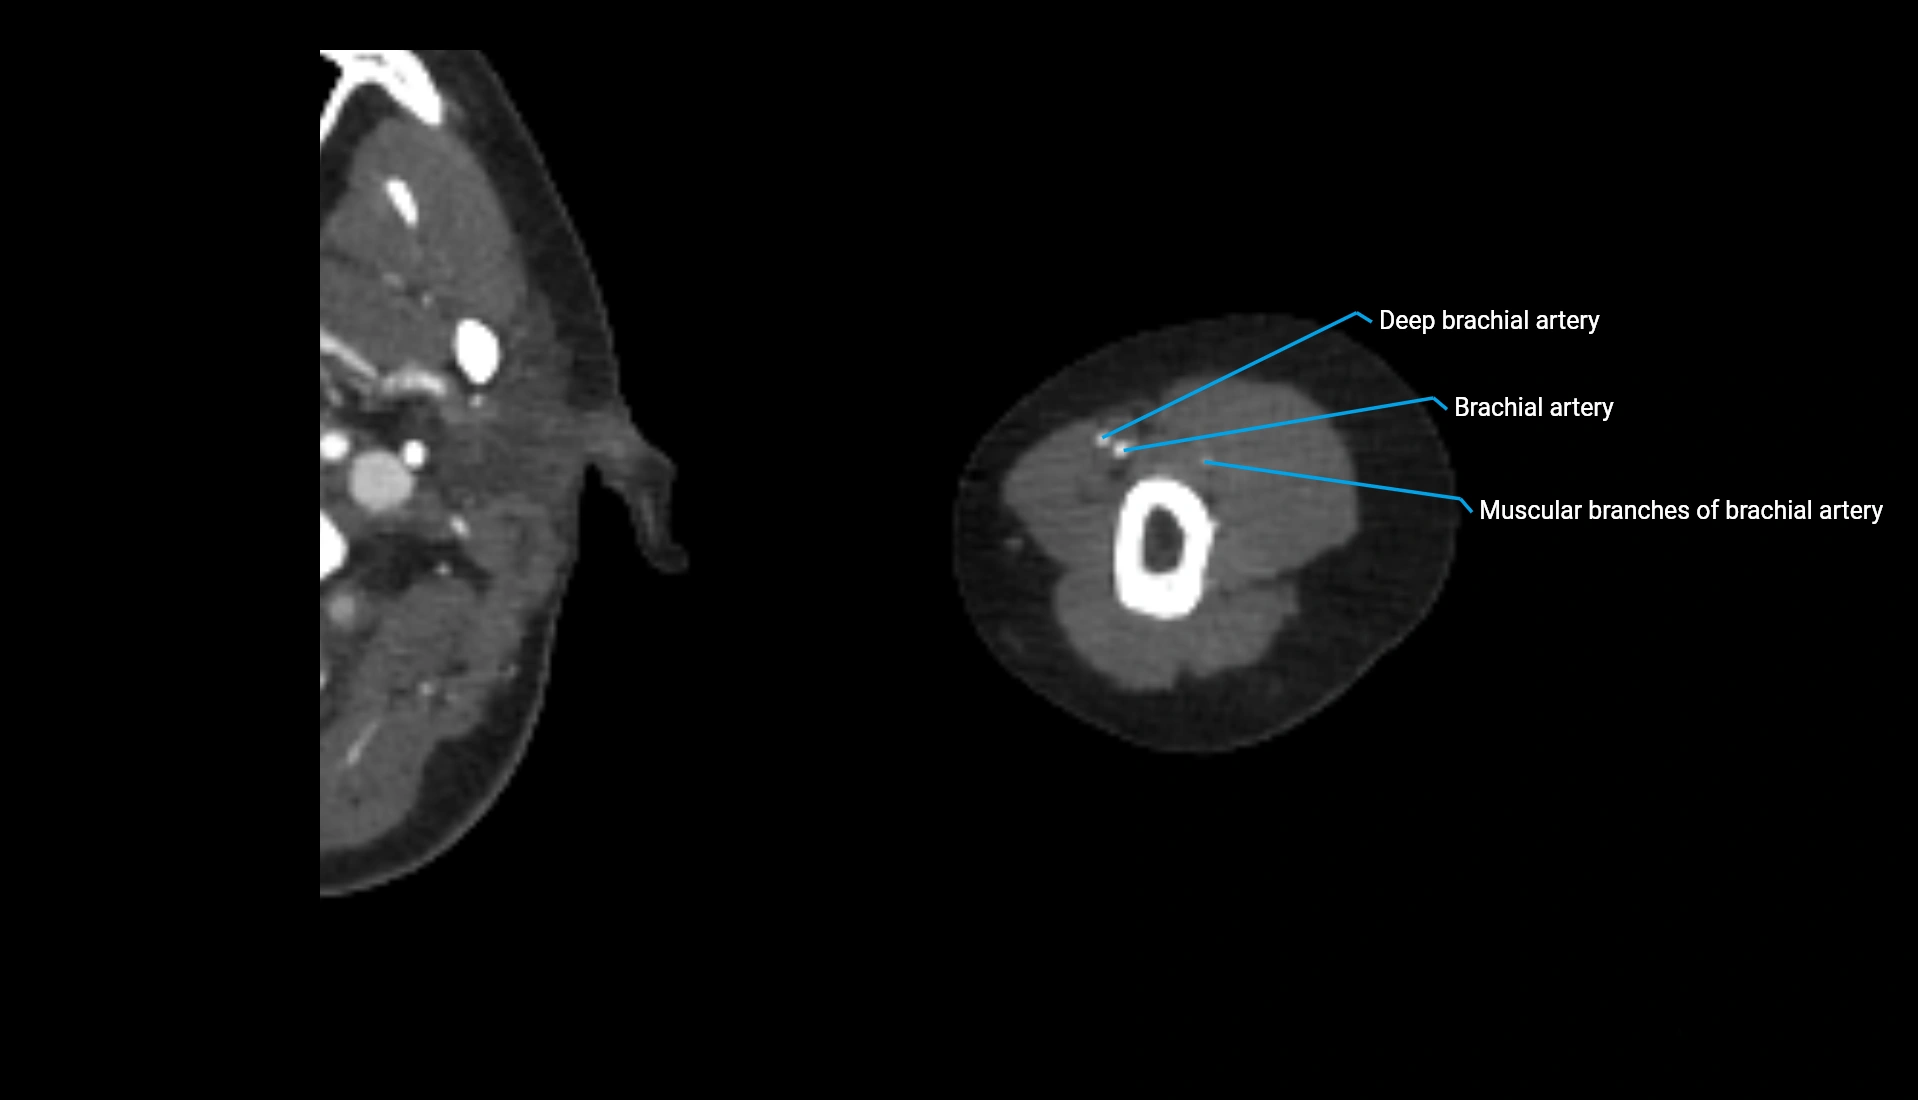

CT Appearance

Non-Contrast CT:

• Cortex: High-density, sharply defined

• Subchondral bone: Dense cancellous matrix

• Articular surface: Smooth concave contour articulating with the capitellum

• Excellent for evaluating bone integrity, alignment, and subtle fractures